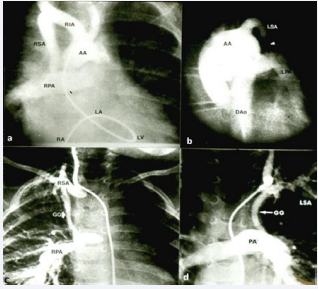

Figure 19 Selected cine frames of angiograms in postero-anterior projection in patients with tricuspid atresia who have undergone classic (a and b) and modified (c and d) Blalock-Taussig shunts. Apart from demonstrating the shunts, the angiographic fames show pulmonary artery (PA) anatomy. Also, note marked narrowing of the left Blalock-Taussig shunt in b. AA, arch of the aorta; DAo, descending aorta; GG, Gore-Tex graft; LA, left atrium; LV, left ventricle; LPA, left pulmonary artery; LSA, left subclavian artery; RA, right atrium; RIA, right innominate artery; RPA, right pulmonary artery; RSA, right subclavian artery [38].

Figure 19: Selected cine frames of angiograms in postero-anterior projection in patients with tricuspid atresia who have undergone classic (a and b) and modified (c and d) Blalock-Taussig shunts. Apart from demonstrating the shunts, the angiographic fames show pulmonary artery (PA) anatomy. Also, note marked narrowing of the left Blalock-Taussig shunt in b. AA, arch of the aorta; DAo, descending aorta; GG, Gore-Tex graft; LA, left atrium; LV, left ventricle; LPA, left pulmonary artery; LSA, left subclavian artery; RA, right atrium; RIA, right innominate artery; RPA, right pulmonary artery; RSA, right subclavian artery [38].

Subsequent to the stabilization of the baby, other ways of providing a more permanent blood flow to the lungs should be sought. Following the initial description of subclavian artery-toipsilateral pulmonary artery anastomosis in 1945 by Blalock and Taussig [60], a number of other types of operations/procedures have been developed to increase the pulmonary blood flow as detailed elsewhere [28,32,35]. Most cardiologists/surgeons at present prefer a modified Blalock-Taussig (BT) shunt with a Gore-Tex graft interposed between the subclavian artery and the ipsilateral pulmonary artery, described by de Leval and his associates [61]. The current thinking suggests that modified BT shunt [61], is probably most attractive procedure to adequately augment pulmonary blood flow. Some surgeons favor central, aorta to pulmonary Gore-Tex tube grafts instead. In a rare patient with principal obstruction at the level of pulmonary valve, balloon pulmonary valvuloplasty may be utilized [62,63]. A more physiologic approach of enlarging the VSD advocated by Annechino [64], is not favored by most surgeons because it is an open-heart procedure. Ductal stenting is an attractive nonsurgical alternative and is being used at some pediatric cardiology centers [65-67]. However, because of the technically demanding nature of the procedure, limited experience, and poor stent patency at follow-up [68], stenting is not currently the procedure of choice. Echocardiographic and angiographic images of some of these procedures are shown in Figures 18 to 20.